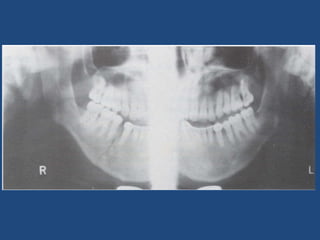

Diagnostic Strategies Midface or maxillary  fractures: Water’s or occipitomental veiw (stable patient). CT scan if: +ve plain x-ray , unstable patients and complex fractures. ( corononal and sagittal or 3 dimension reconstruction) Mandible injuries: Panorex radiographs. Coronal CT for condyle fractures.

Mandible Fractures Clinical findings Mandibular pain. Malocclusion of the teeth Separation of teeth with intraoral bleeding Inability to fully open mouth. Preauricular pain with biting.  Positive tongue blade test.

• #37 These fractures manifest clinically with mandibular pain, tenderness and malocclusion. A step off in the dental line or ecchymosis to the floor of the mouth are often present and is highly suggested of a mandibular fracture. Patients are unable to fully open their mouth. Patients may have preauricular pain with biting when there is a fracture of the condyle. Picture 1: The open fracture line is evident clinically. There is slight mal-alignment of the teeth. Picture 2: Hemorrhage or ecchymosis in the sublingual area is pathognomonic for an mandibular fracture.